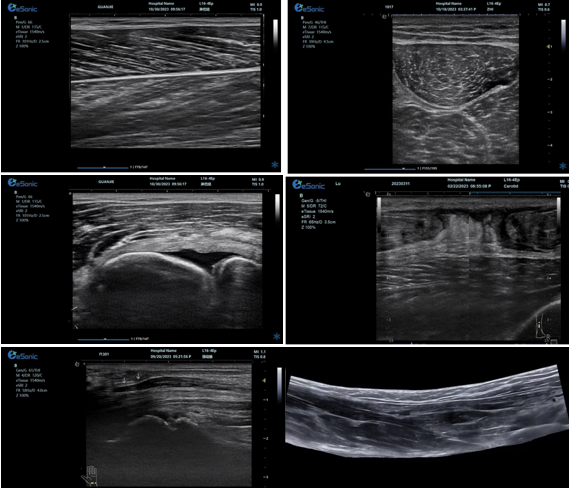

优异的图像质量

0ab1c76ef15f937a5e743335fd068cc.png

肌骨超声精确评估解决方案:

1、肌肉、肌腱、韧带专业评估

2、骨及软骨、滑膜及滑囊专业评估

3、神经病变及相关疾病临床应用

4、超声引导下可视化穿刺治疗

5、超声引导下可视化冲击波治疗